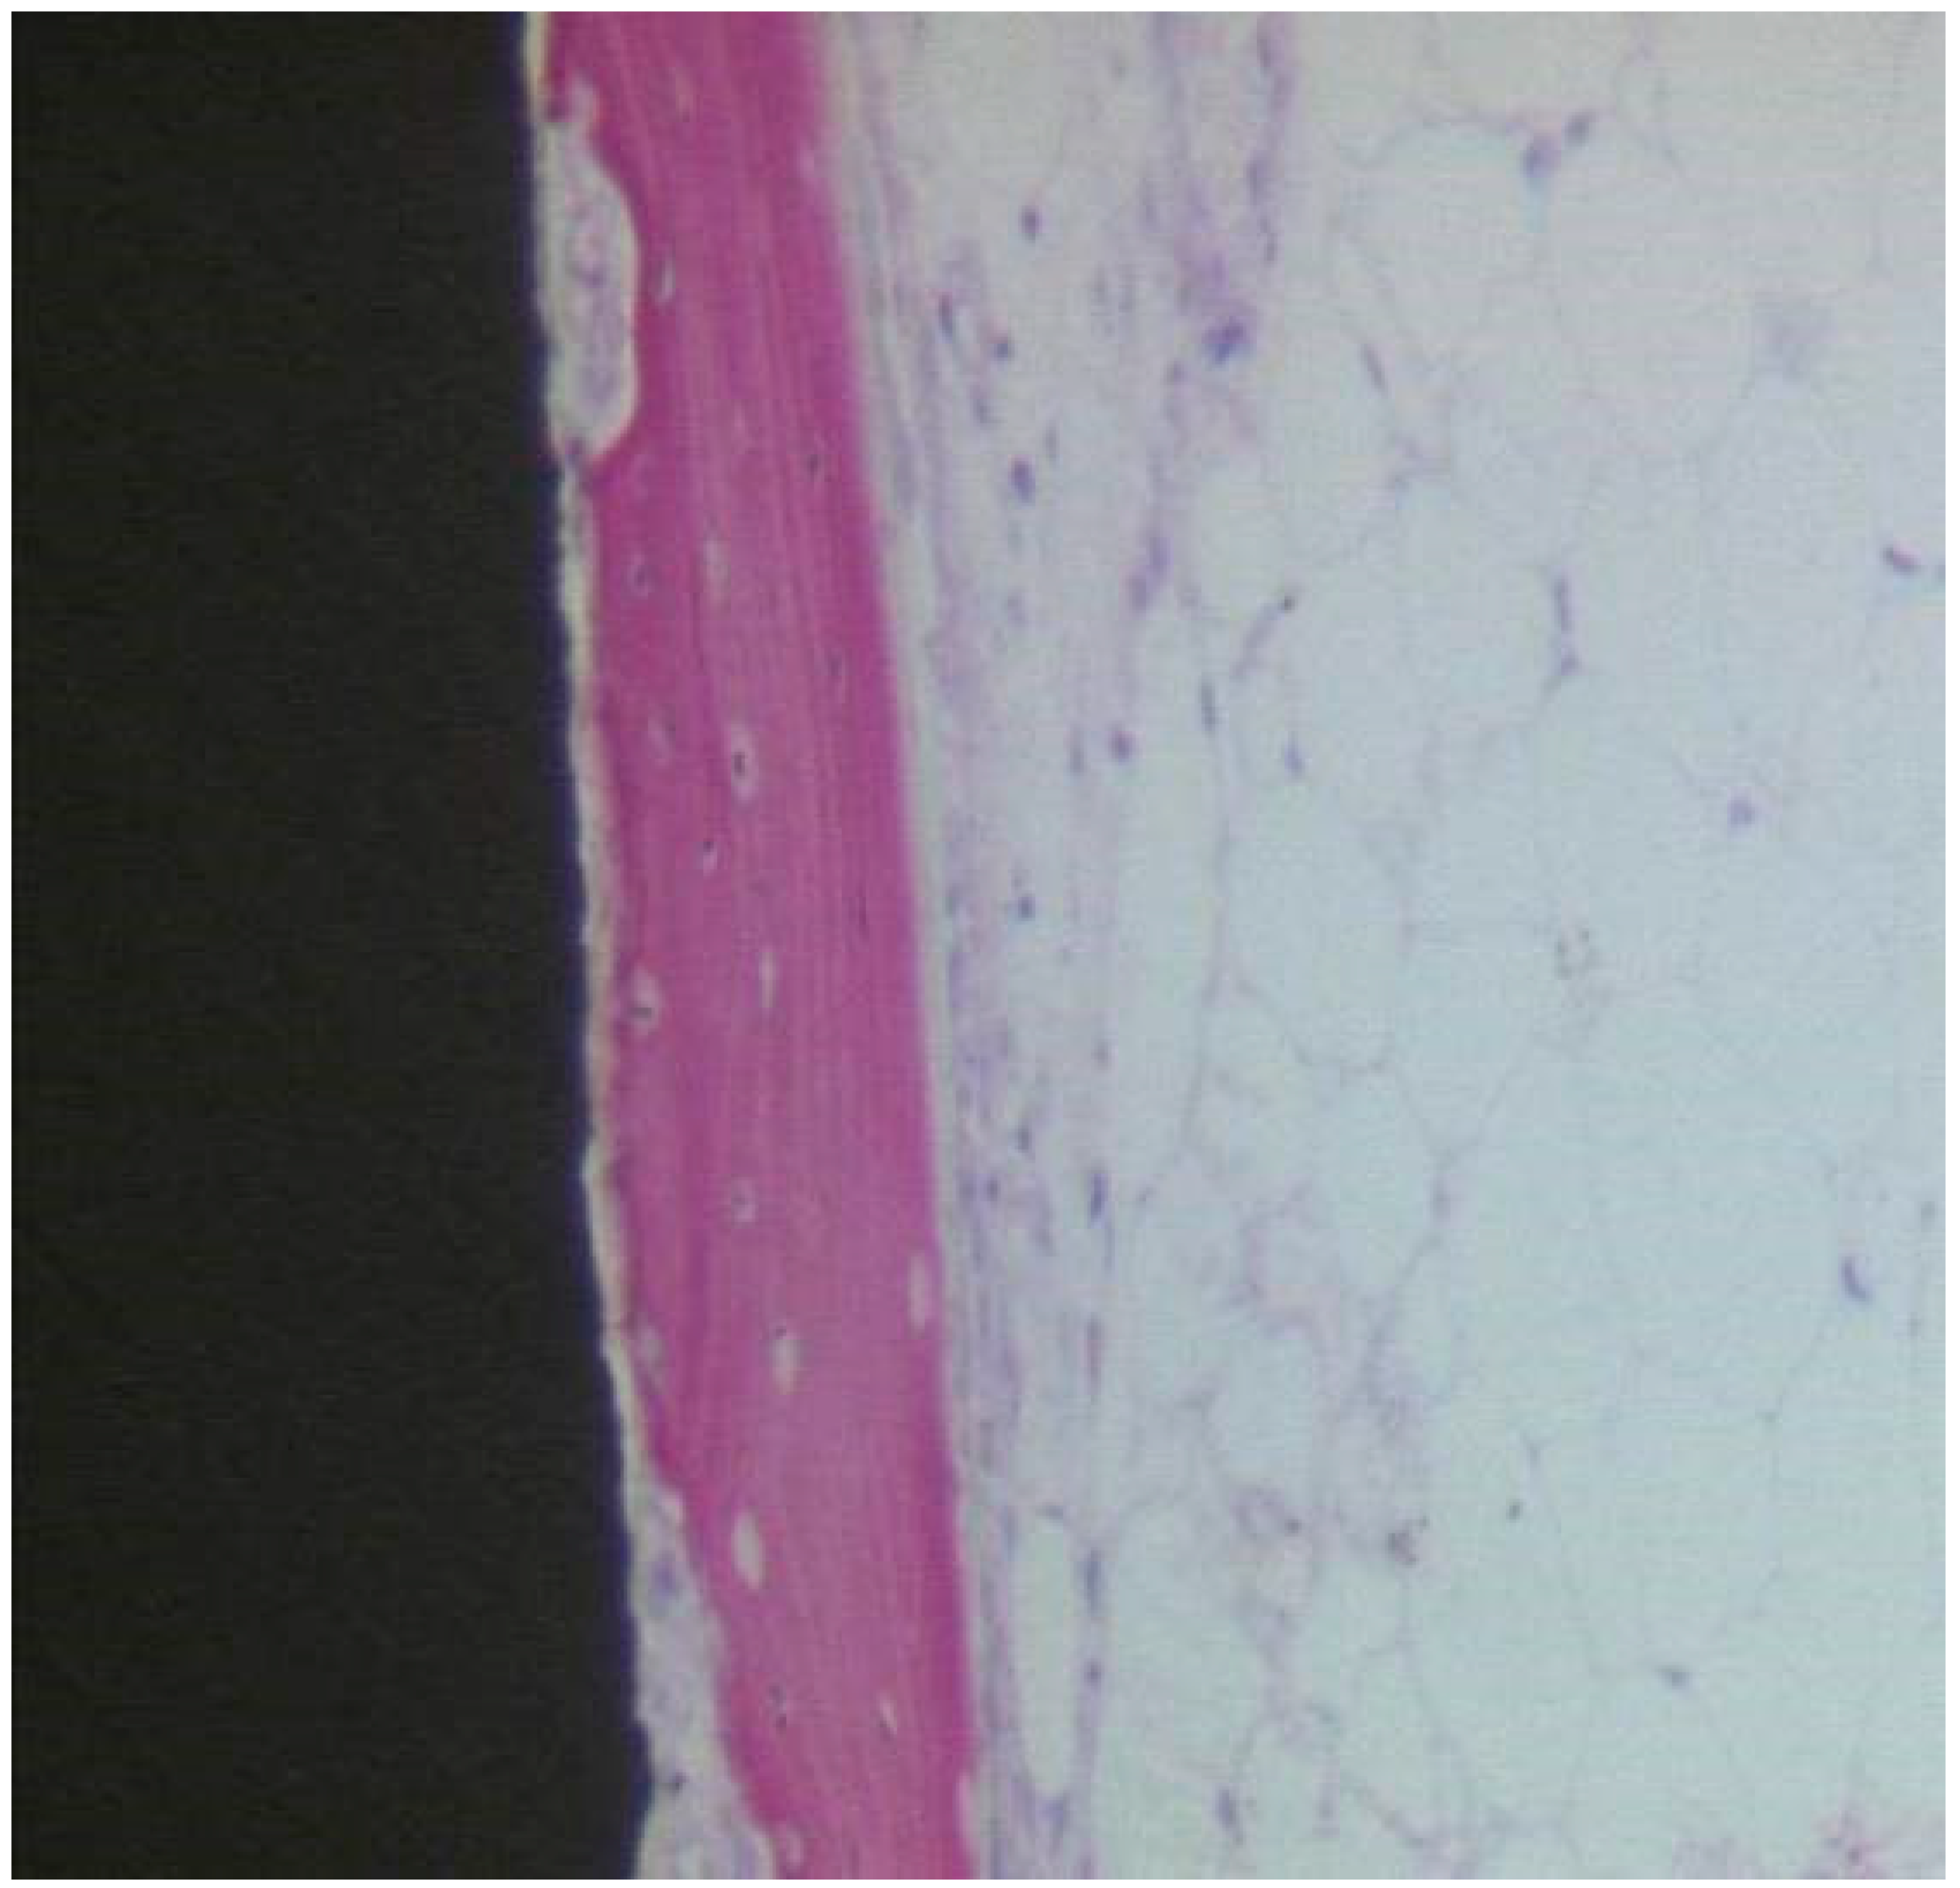

Uncoated Implant Surface